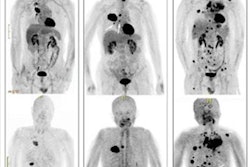

The incidental detection highlights the high sensitivity of FAPI-PET for detecting previously unknown tumors, noted a team led by Dr. Timur Sellmann of the Evangelical Hospital Bethesda in Duisburg.

"This report demonstrates the high sensitivity of Ga-68 FAPI-PET/CT to detect previously unknown tumors, making it a promising test in cases of suspected tumor disease or in cancers of unknown primary," the group concluded.